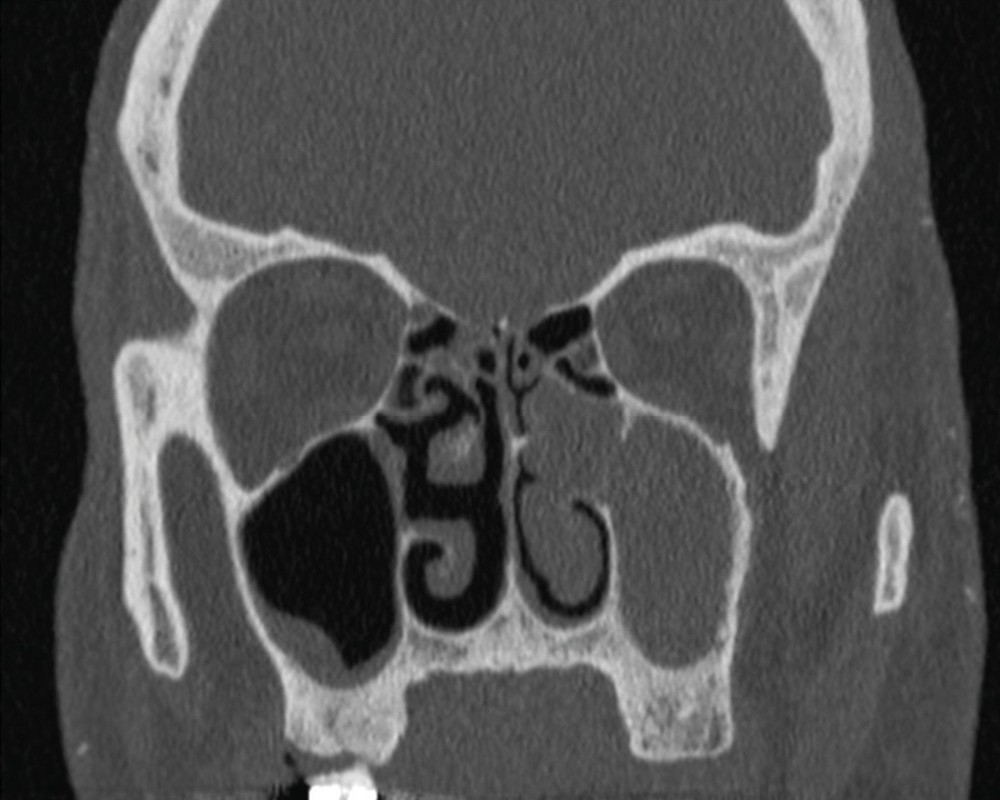

La tomodensitométrie des sinus retrouve un comblement complet unilatéral du sinus maxillaire gauche et des cellules ethmoïdales antérieures homolatérales, sans image de densité calcique intrasinusienne et sans lyse osseuse des parois (fig. 1). L’IRM montre un épaississement tissulaire de 23 mm de grand axe en regard du méat moyen gauche, avec un aspect de signal T2 hétérogène (fig. 2) et prenant le contraste en masse (fig. 3). Le comblement maxillaire gauche associé à un épaississement muqueux en cadre rehaussé correspond à une rétention en hypersignal en diffusion (fig. 4), avec diminution du coefficient apparent de diffusion (moyenne à 433 mm2/s) en faveur d’une pyocèle (fig. 5).